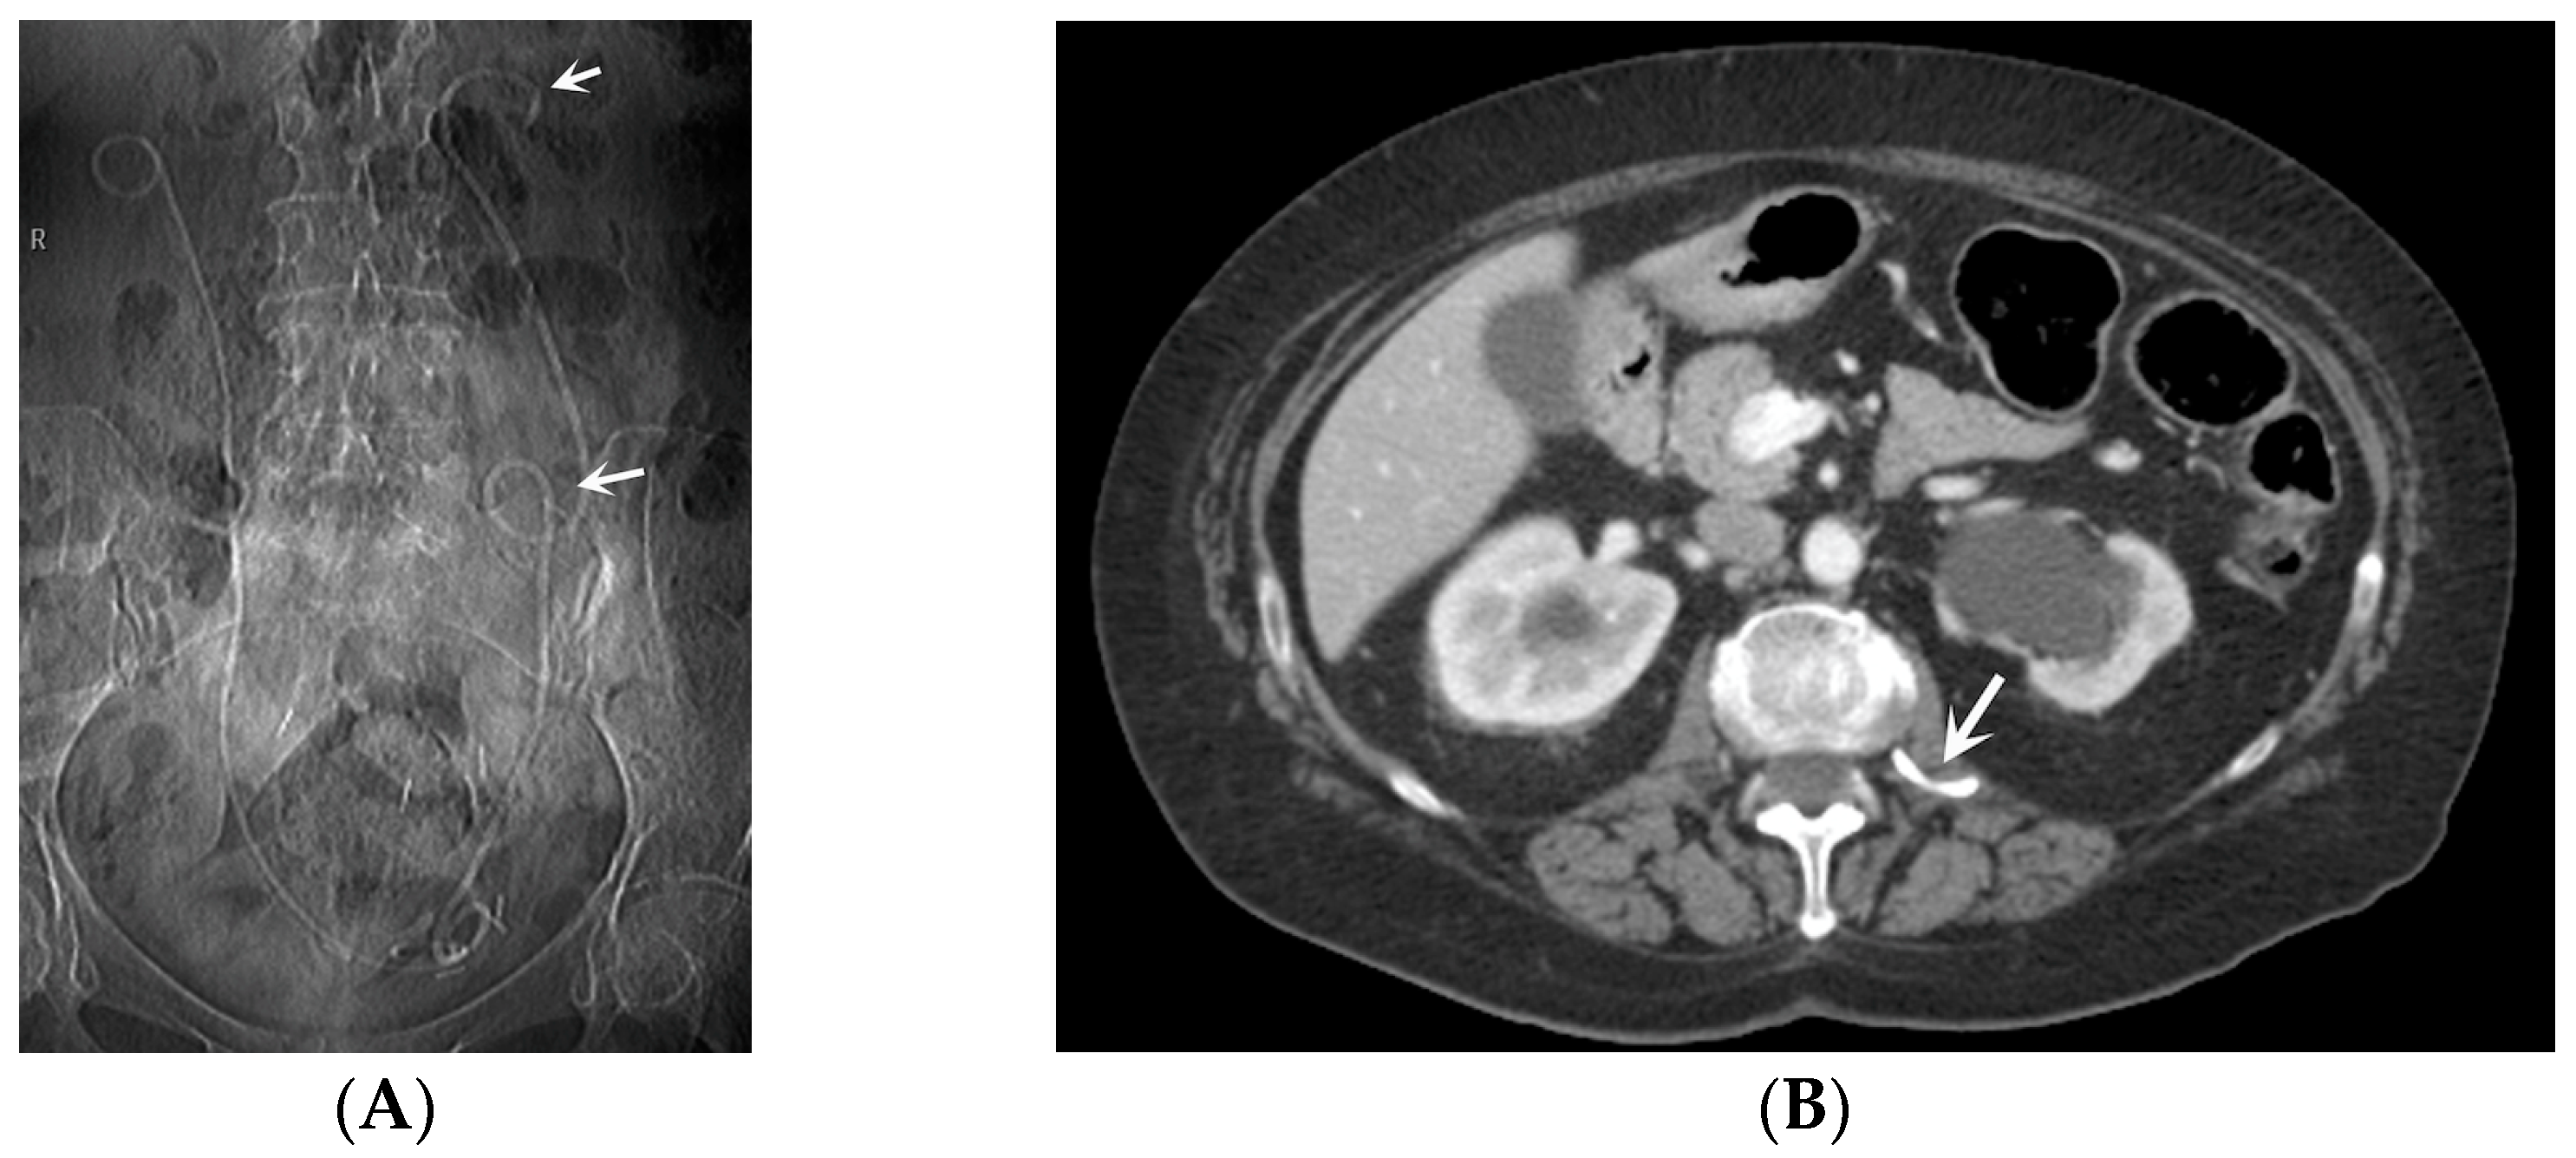

- Urine leakage: Stents crafted from more rigid materials have the potential to perforate the ureter, collecting system, and kidney parenchyma during placement, leading to the formation of fluid collections or urine leakage, often resulting in a urinoma [35] (Figure 9). A urinoma is a collection of extravasated urine outside of the urinary tract. The optimal diagnostic imaging studies for this condition include contrast material-enhanced CT with delayed imaging (10–20 min), CT–cystography, and a retrograde urethrography [36,37]. In a CT scan, a urinoma may manifest as a restricted or unrestrained collection within the intra- or retro-peritoneal compartment, with the latter occurrence being more prevalent. Its attenuation values can vary from 0 to 20 HUs before the administration of intravenous contrast, subsequently intensifying up to 200 HUs after contrast administration (Figure 9). The irritation from the urine may lead to the formation of a fibrous capsule surrounding the urinoma, which can occasionally become calcified. Not infrequently, a dystrophic calcification of the urinoma may occur, which results from an inflammatory and fibrotic reaction to the extravasated urine [38]. Urinomas, typically small initially, are often resolved on their own without intervention. However, in cases of significant injury or a larger urinoma failing to reabsorb, urological or interventional radiological procedures may be necessary. Neglecting intervention can lead to complications, such as abscess, electrolyte imbalance, hydronephrosis, and urosepsis [37,38].